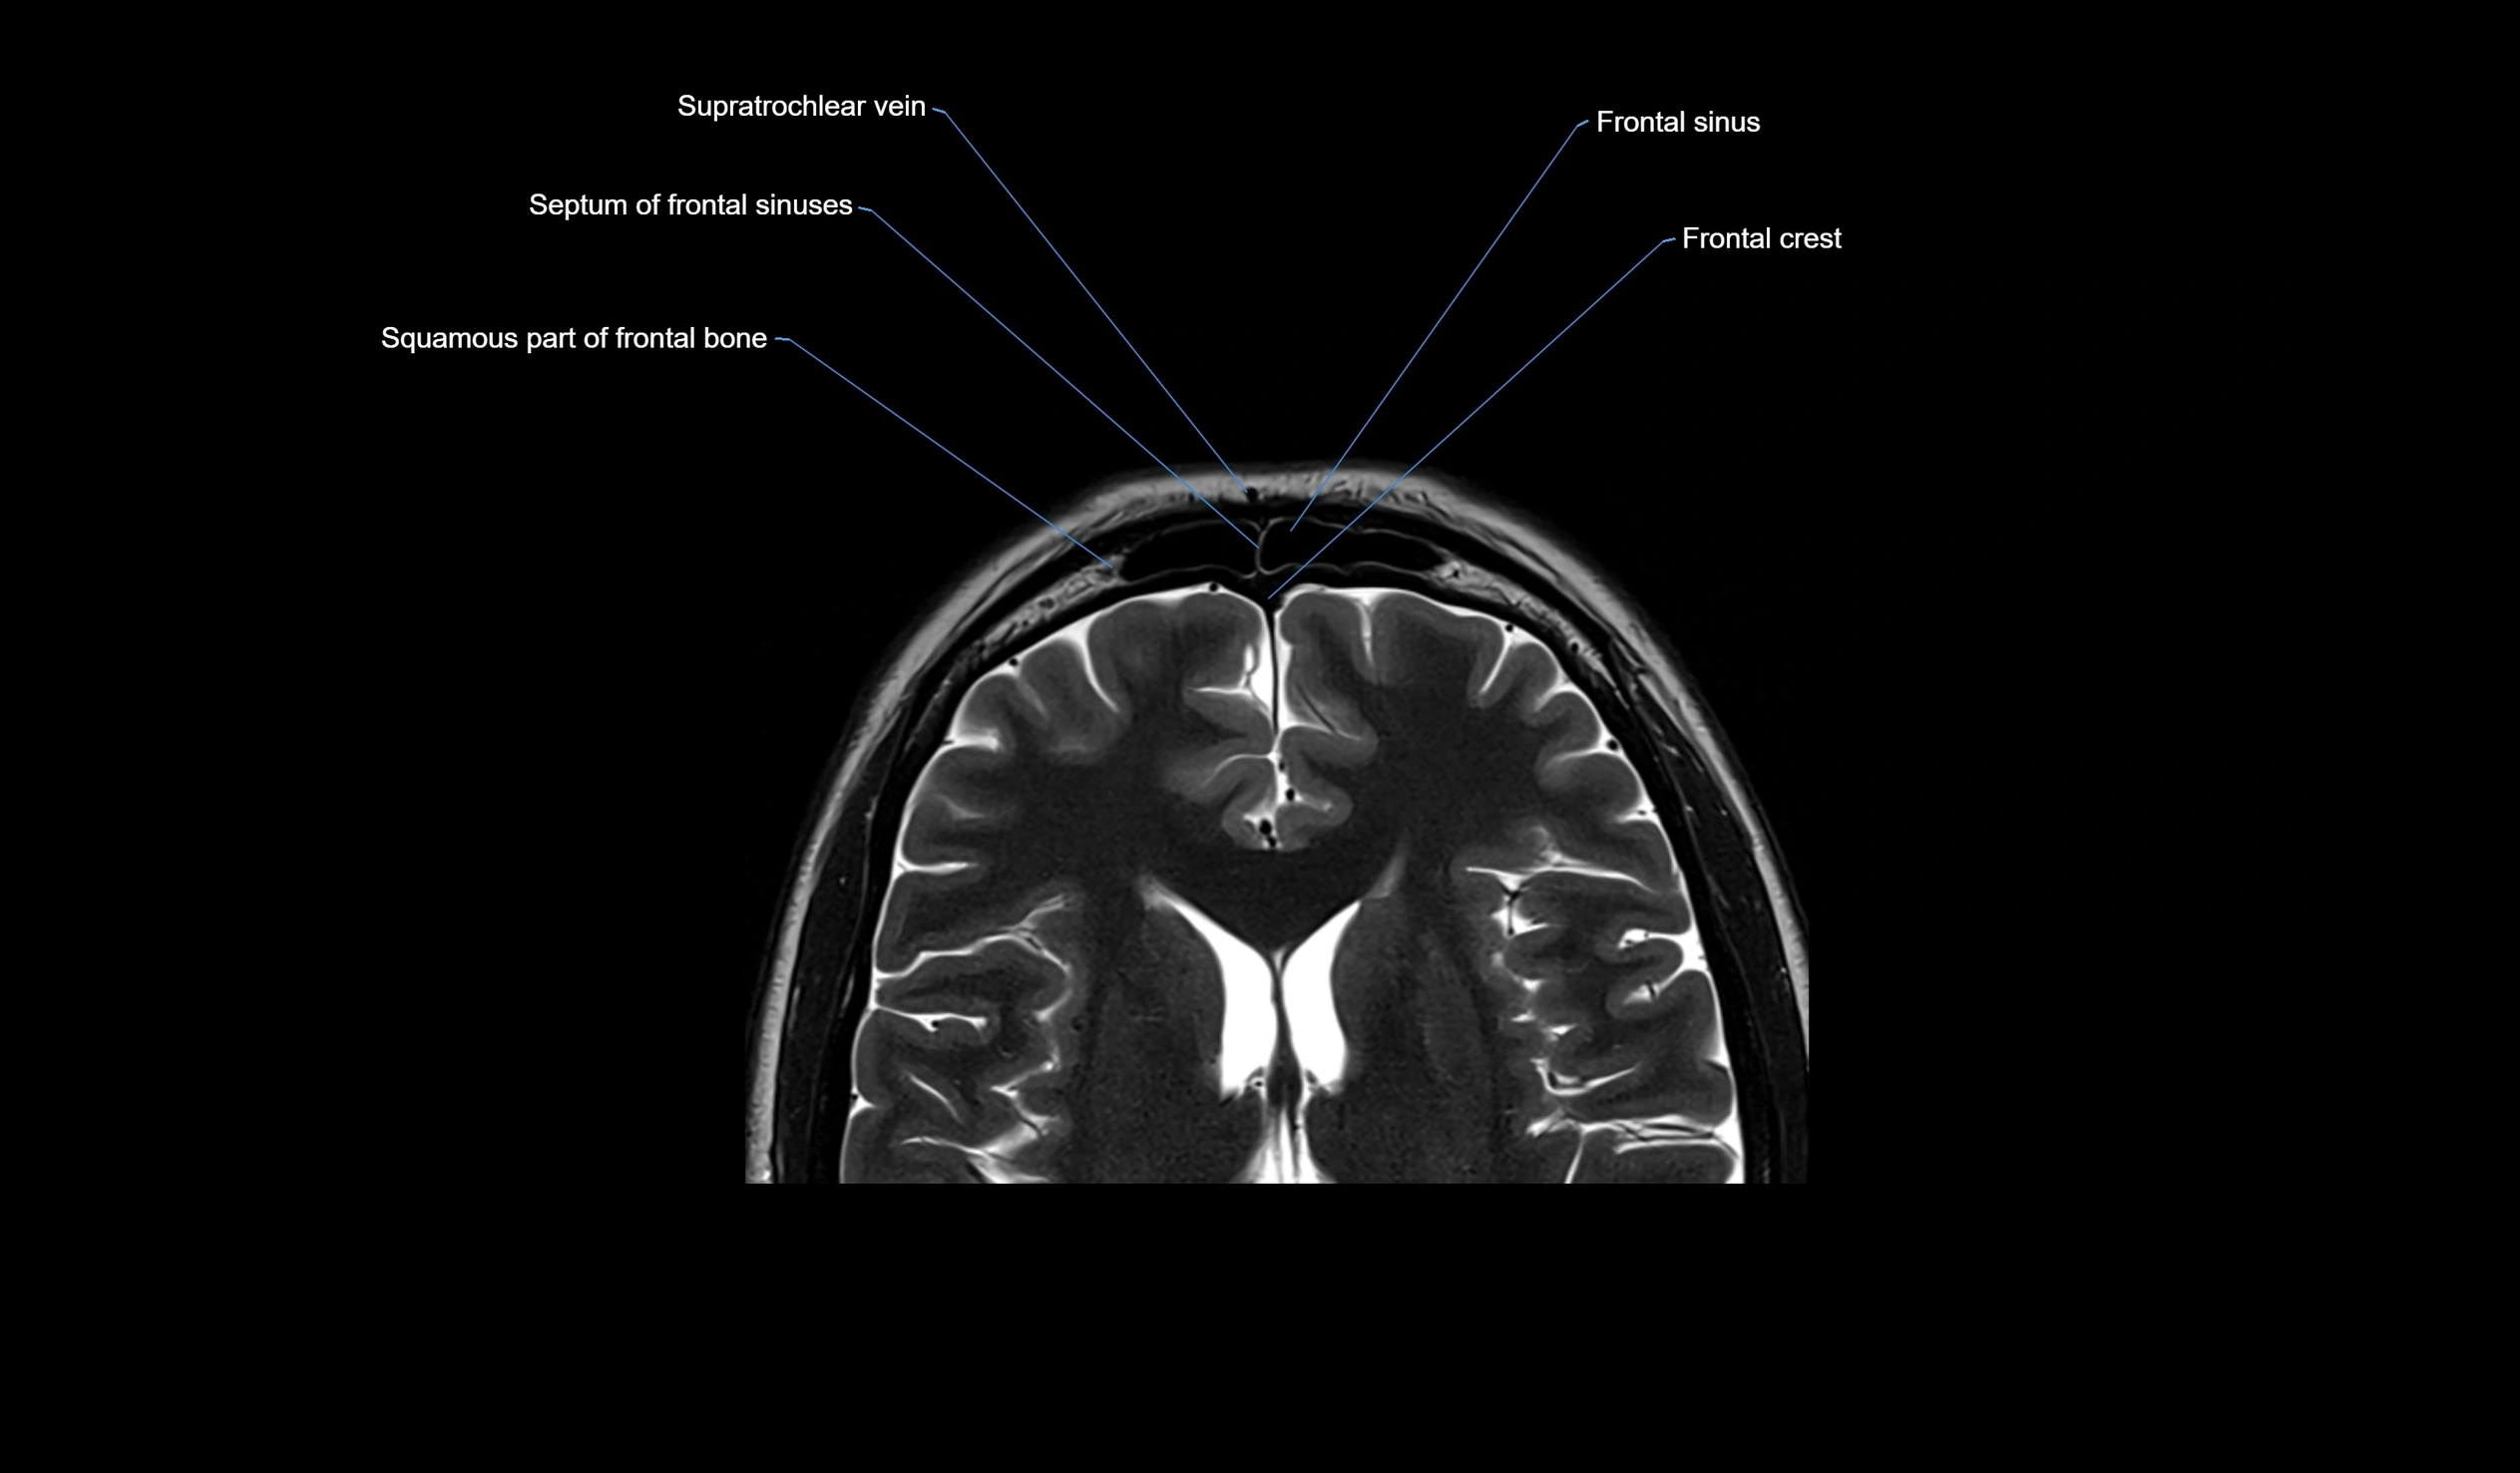

- Frontal sinus

- Supratrochlear vein